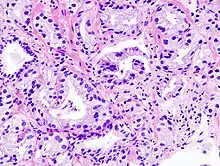

عواملی که خطر ابتلاء به سرطان پروستات را افزایش میدهند سن بالا، سابقهٔ خانوادگی بیماری، و نژاد میباشد. حدود ۹۹ درصد موارد در افراد بالای ۵۰ سال رخ میدهد. اگر یکی از خویشاوندان درجه اول به این بیماری مبتلا شده باشند، احتمال ابتلاء به بیماری دو تا سه برابر میشود. این بیماری در ایالات متحده بیشتر در میان سیاهپوستان آمریکا بروز پیدا میکند تا سفید پوست. دیگر عوامل دخیل در این بیماری شامل این موارد نیز هست: رژیم غذایی با سطوح بالای گوشت فرآوری شده، گوشت قرمز یا فراورده لبنی یا رژیمهای غذایی که سبزیهای خاصی را در خود ندارند.[2] سرطان پروستات از طریق بافت برداری تشخیص داده میشود. تصویربرداری پزشکی نیز ممکن است بعداً انجام شود تا مشخص شود که آیا سرطان به دیگر بخشهای بدن سرایت کردهاست یا نه.[5]